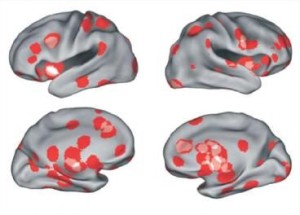

Pour mener l’enquête, plusieurs équipes de recherche ont travaillé très sérieusement à l’aide d’une machine qui a révolutionné l’imagerie cérébrale : l’IRM fonctionnelle. Basée sur l’observation de l’hémoglobine, elle permet d’observer l’afflux de sang vers une zone du cerveau particulière, synonyme d’une activité accrue. Il est alors possible d’identifier par ce biais les zones du cerveau impliquées dans différents processus. Une étude récente a d’ailleurs indiqué avoir pu identifier la zone du cerveau dédiée au courage, alors pourquoi ne pas repérer la ou les zones liées à l’amour ?

Au cours de six études, la modification de l’activité cérébrale avait été mesurée au total sur 120 personnes à qui l’objet de leur amour avait été présenté. Ces travaux déjà publiés dans la littérature scientifique ont été regroupés au sein d’une méta-analyse par des chercheurs de l’université de Syracuse. En analysant de nouveau tous ces documents, ils ont pu montrer que le coup de foudre est un processus très court puisqu’il se déroule en seulement un cinquième de seconde !

Lorsqu’une personne tombe amoureuse, pas moins de 12 régions du cerveau s’activent (impliquées dans l’émotion, la motivation, la récompense, la cognition sociale…) pour libérer des molécules chimiques euphorisantes comme la dopamine, l’ocytocine, l’adrénaline et la vasopressine. Tomber amoureux peut donc engendrer les mêmes effets que ceux produits par la cocaïne. On comprend alors mieux pourquoi une certaine dépendance peut s’établir entre les deux individus d’un couple amoureux.

Toutefois, les différents types d’amours ne sollicitent pas les mêmes zones du cerveau. Ainsi, dans le cas d’amour inconditionnel comme celui d’une mère pour son enfant, la perception de l’être aimé n’active pas les mêmes zones (substance grise périaqueducale, régions corticales impliquées dans la cognition ou l’émotion de haut niveau) que lors d’un amour passionnel.